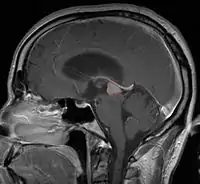

Pineal Gland Tumors

Clinical Presentation

- Determined by the spatial anatomy and direction of growth

- Obstruction of aquaduct: hydrocephalus presenting as headaches, nausea, vomiting

- Compromise of superior colliculus: vertical gaze palsy, pupillary and oculomotor nerve paresis (Parinaud syndrome)

- Progressive growth: cranial nerve neuropathies, hypothalamic dysfunction